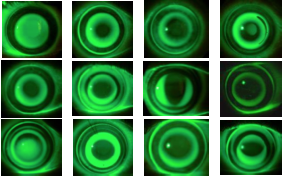

El curso fue desarrollado con un carácter puramente práctico y se analizaron gran cantidad de fluorogramas y topografías tras tratamiento con OrtoK entre todos los asistentes.

El curso fue desarrollado con un carácter puramente práctico y se analizaron gran cantidad de fluorogramas y topografías tras tratamiento con OrtoK entre todos los asistentes.